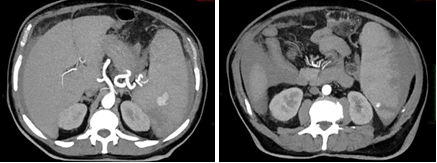

On October the 26th the patient was admitted in ER for worsening of general malaise and fatigue. Chest’s CT scan revealed lobar pneumoniae and antimicrobial therapy with ceftriaxone and clarithromycin had started. Blood test results showed Hb 11.7 gr/dl, WBC 27.120/, lymphocyte 20.000/mmc, platelet count 86.000/mmc. On October the 30th a second ER admission was required for acute abdominal pain. Abdominal CT scan revealed splenic artery’s pseudoaneurysm, large ruptured of subcapsular splenic hematoma >50% and hemoperitoneum. Splenic artery embolization was performed. 24 h after the onset CT control showed increasing splenic volume with 80% of ischemic rate. Therefore, urgent splenectomy and partial pancreatectomy was demanding.

Figure 2. TC October 2022: Pseudoaneurysm and hemoperitoneum previous embolization.

Figure 3. TC October 2022: Pseudoaneurysm and hemoperitoneum previous embolization.